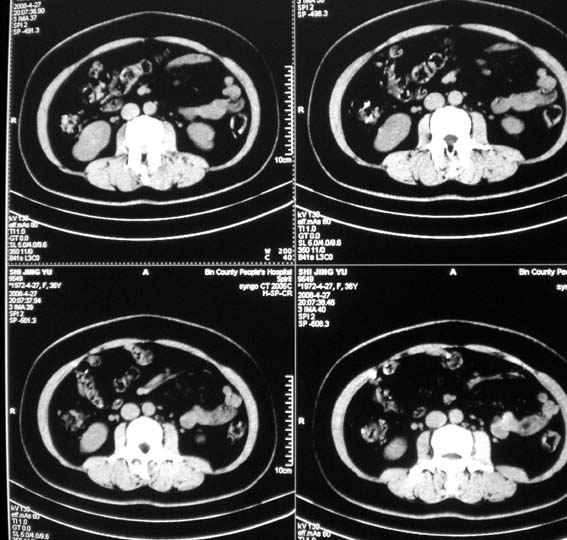

标题: CT13126:腰痛,肾区痛。 [打印本页]

标题: CT13126:腰痛,肾区痛。

女,36岁,腰痛,肾区痛曾有肾囊肿史。

中上腹部ct平扫未见明显异常。

可行强化帮助检查